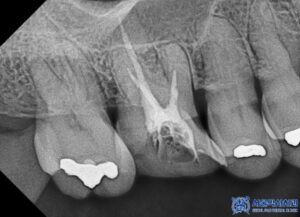

환자분은 좌측 아래쪽 어금니가 없는 상태였고,

오랫동안 방치되어 치조골(잇몸뼈)의

변화가 일부 있었습니다.

하지만 다행히도 임플란트를 식립하기에

충분한 골량이 유지되고 있었고,

임플란트 치료 외에도, 환자분의 남아있는

치아들 중 심한 충치가 있는 어금니

(오른쪽 위 큰 어금니, 왼쪽 위 작은 어금니,

왼쪽 위 큰 어금니, 왼쪽 아래 큰 어금니)는

신경치료를 진행하였습니다.

특히, 신경치료 시 일반적인 충전재(고무) 대신

MTA 신경치료를 적용하였습니다.